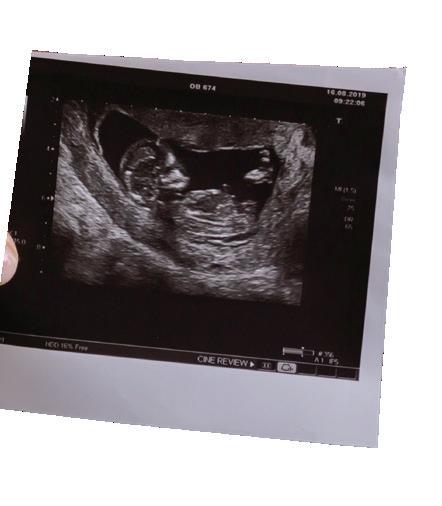

Am I Pregnant?

Pregnancy tests are not always accurate. Protect your health and get your pregnancy confirmed with an ultrasound. It can show if the baby is in the uterus and has a heartbeat and how far along you are. Going through an abortion without knowing this is risky.

A significant number of early pregnancies end on their own in miscarriage and a smaller number grow in the wrong place-outside of the uterus, which can be life-threatening.4 An ultrasound exam can confirm that your pregnancy is in the uterus and is living. This information is helpful as you make this decision: abortion or continuing with your pregnancy.

Any woman considering the abortion pill should have an ultrasound examination to verify if there is a pregnancy inside the uterus, see if there is cardiac activity, and obtain an estimate of gestational age. Without this critical evaluation, the risk of complications increases significantly.